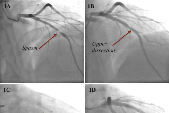

Spontaneous Coronary Artery Dissection and Implantation of Absorb Bioresorbable Drug-Eluting Stent in Cocaine-Related Acute Coronary Syndrome

The spontaneous dissection of the coronary arteries (SCAD) is rare and few data are available in the worldwide literature. Several diseases and conditions have been associated with SCAD, such as atherosclerosis, connective tissue disorders and the peripartum episode. Cocaine addiction is one of causes of the disease in young patients. In this paper we present a case report of a patient with a acute coronary syndrome who had a history of recent cocaine abuse.